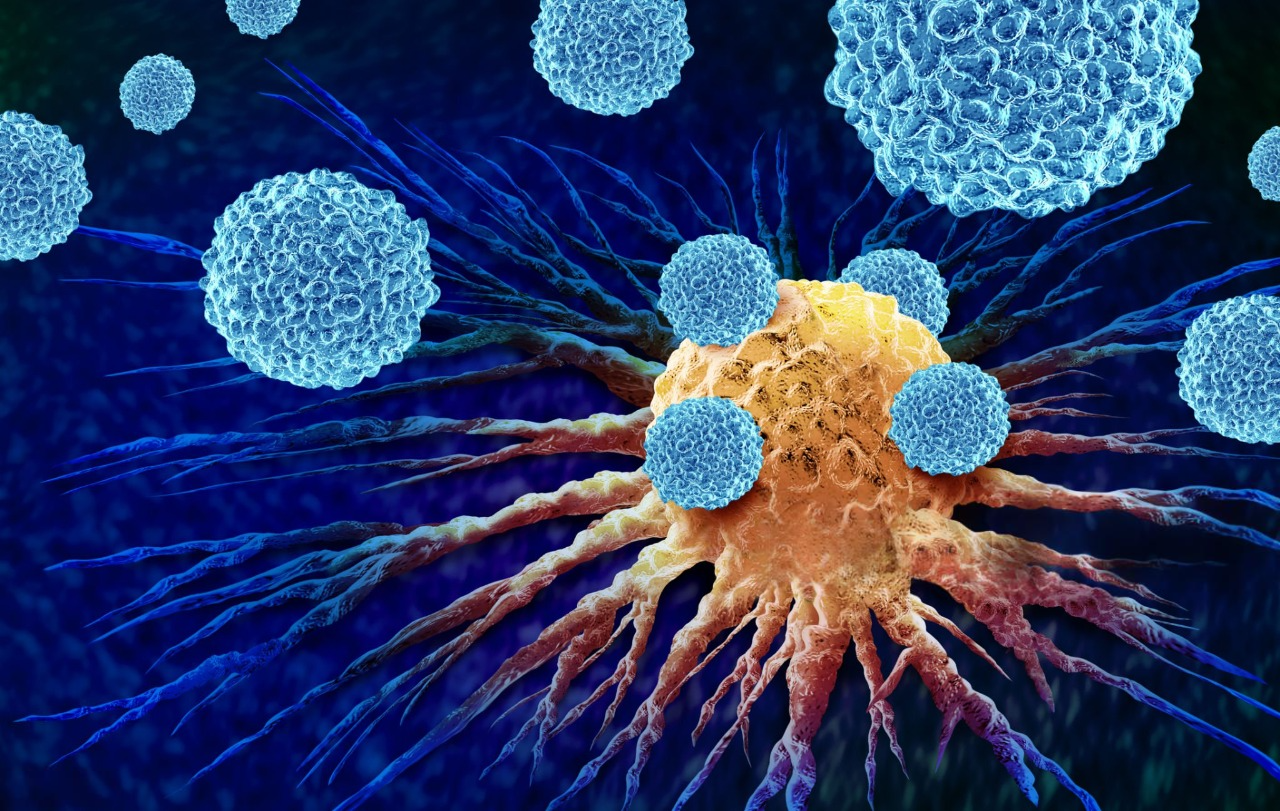

We co-ordinate expert surgical oncology with wholistic multidisciplinary management. From the first consultation to your recovery, we're with you for every step - so you can focus on what matters most: living your life fully and confidently.

Expert Surgeons

Our specialists focus on complex oncological surgeries. Treating you with skill, understanding and compassion before, during and after surgery.

Multidisciplinary Care

Fully integrated cancer care, collaborating with top specialists across Sydney, New South Wales, and beyond.